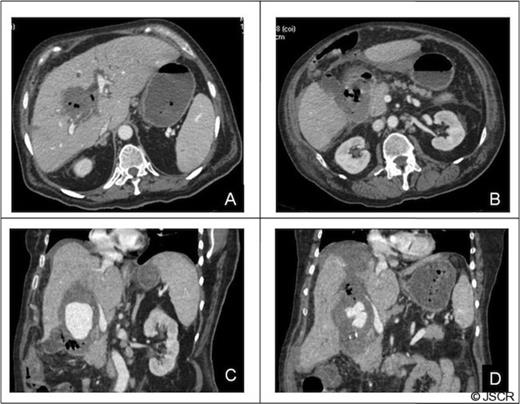

Forty-eight hours after admission the patient had an episode of haemodynamic instability suggestive of septic shock, which was also associated with a drop of 15 points in haematocrit levels (haematocrit: 24, WBC: 33 000). Empirical antibiotic therapy was begun and abdominal contrast-enhanced computed tomography (CT) was performed. CT showed a pseudoaneurysm of the right hepatic artery (RHA) of 7 cm in diameter, haemoperitoneum, intrahepatic dilatation of the biliary tree bile duct and the presence of hepatic infarction, and duodenal wall involvement (Figures 1 and 2).

CT of the abdomen: A) Tridimensional reconstruction, B) Axial slice C) Coronal slice (a;.Pseudoaneurysm of the right anterior hepatic artery, b;Left hepatic artery, c;Common hepatic artery, d;Gastroduodenal artery). The right posterior hepatic artery arises from the left hepatic artery.